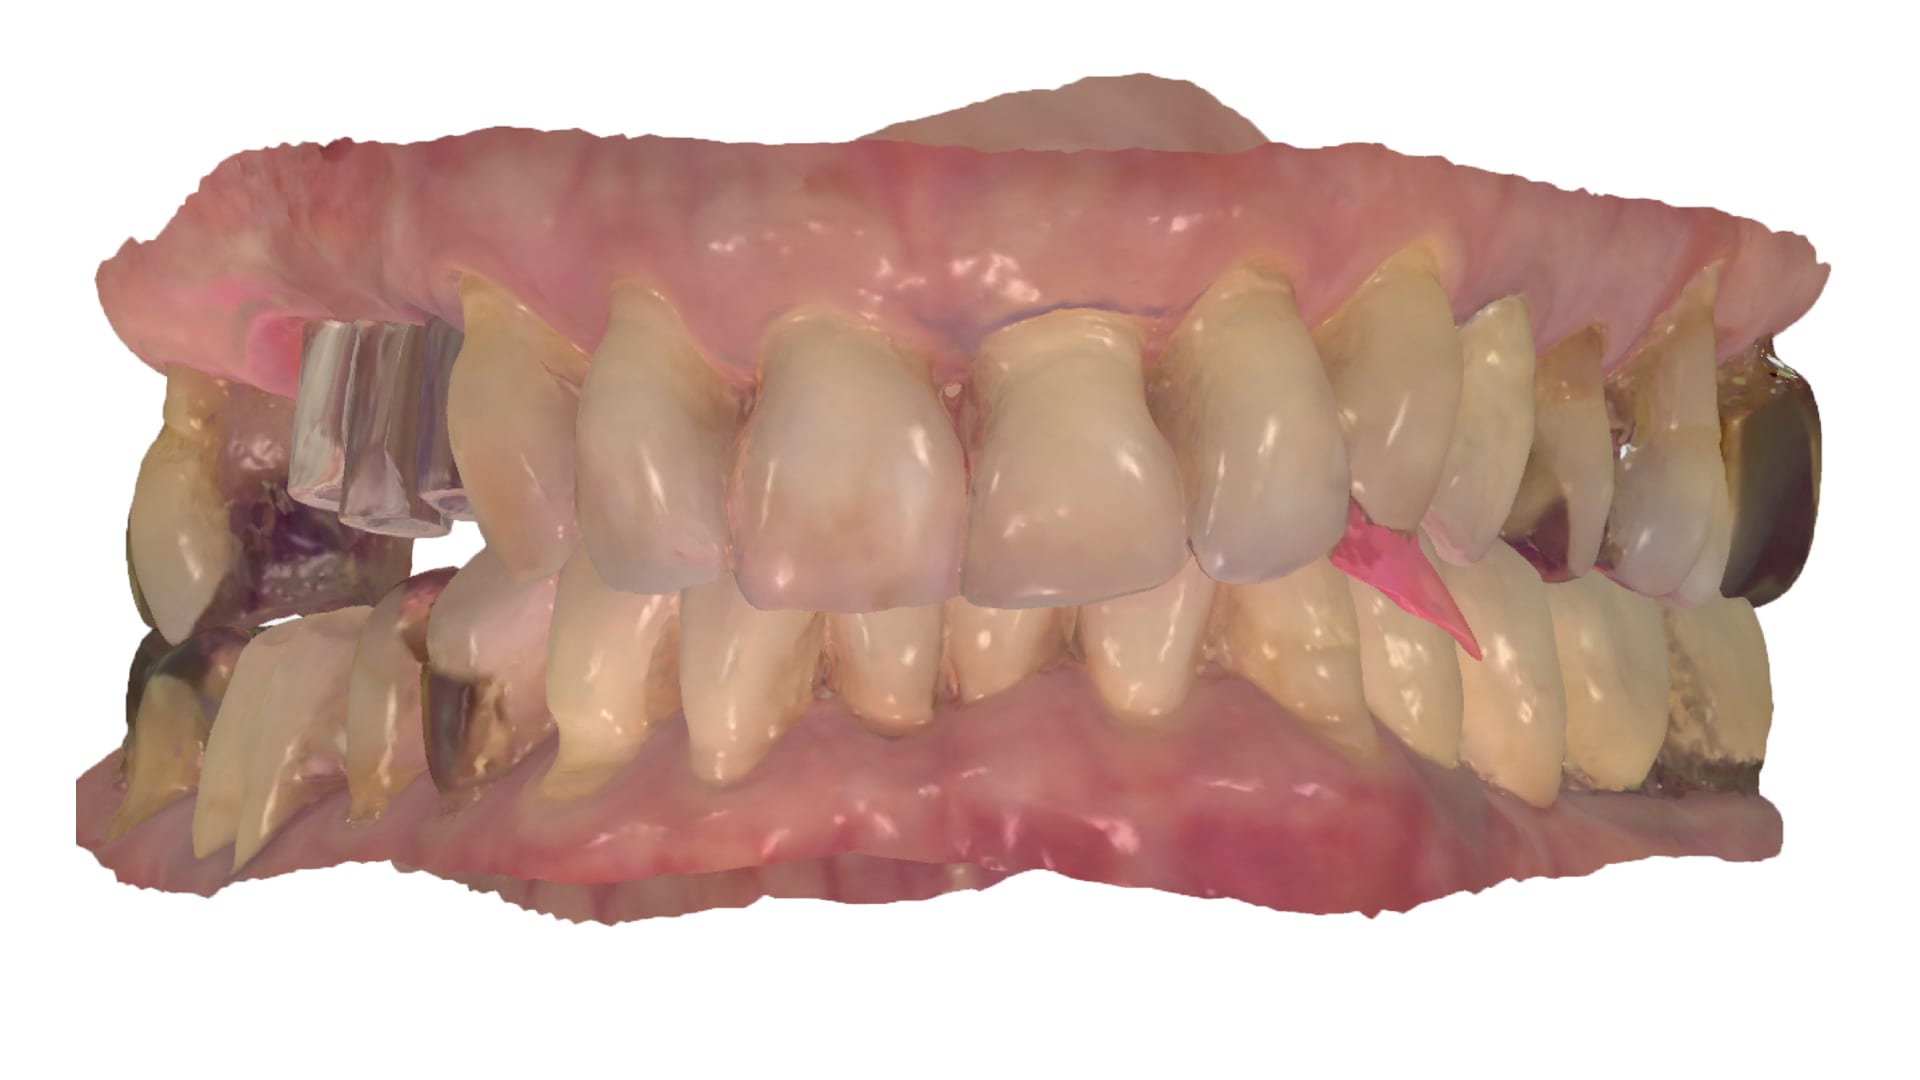

Abb. 4: Intraorale Scandaten in Okklusion

Abb. 5: Intraorale Scandaten vom Oberkiefer

Abb. 6: Intraorale Scandaten vom Unterkiefer